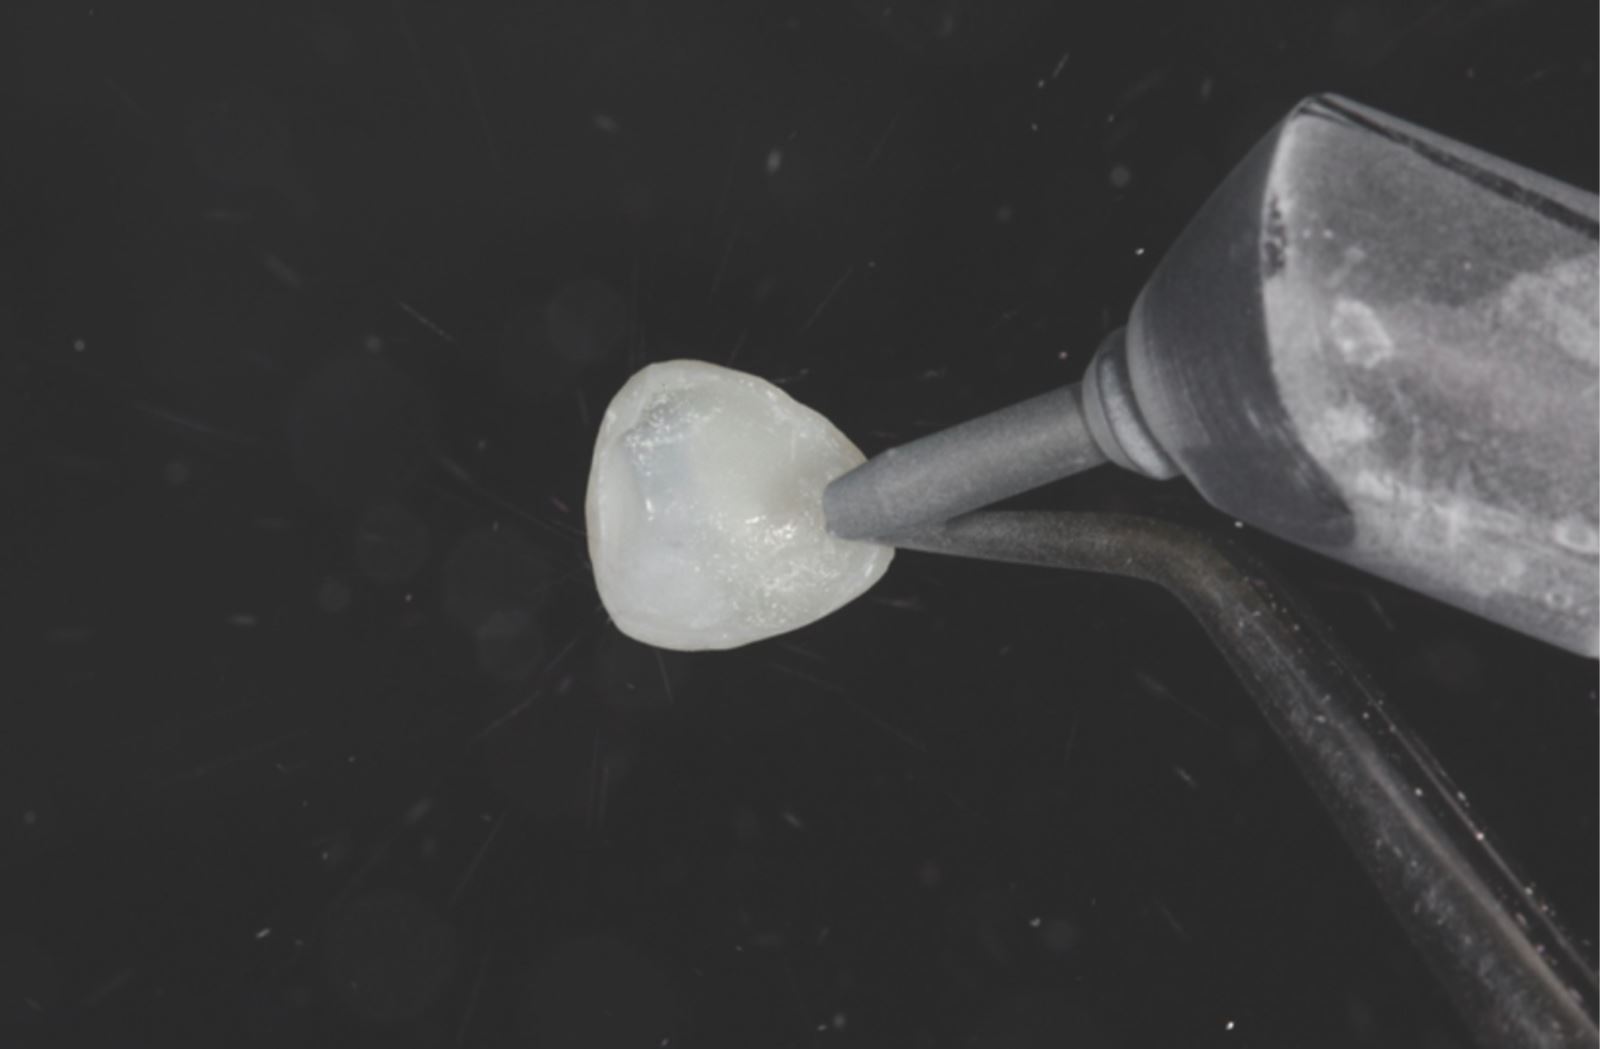

Úprava vnútorného povrchu:

Vnútorný povrch fazety bol pieskovaný. Alternatívne je možné pre tento krok použiť 35% kyselinu fosforečnú Ultra-Etch™.

Vnútorný povrch fazety bol potiahnutý adhezívom Peak™ Universal Bond.

Stenčenie a polymerizácia adhezíva:

Adhezívum bolo stenčené prúdom vzduchu a následne polymerizované svetlom VALO™ X po dobu troch sekúnd v režime Xtra Power.